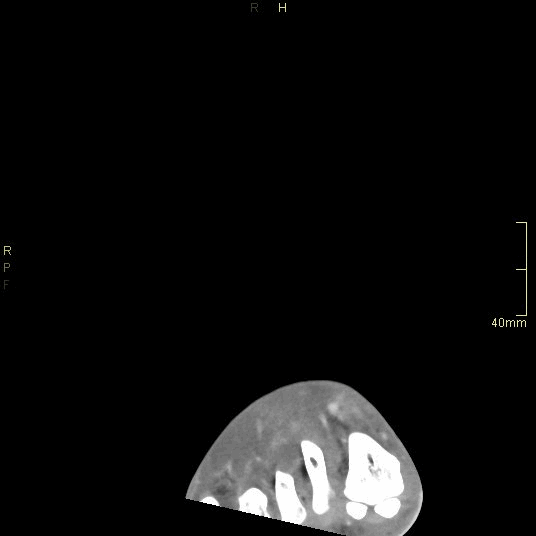

CT Ankle Contrast- Soft tissue window (coronal)

CT Ankle Contrast- Bone window (coronal)